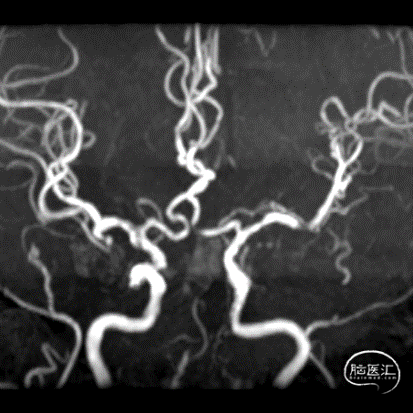

术前MRA未见颅内后循环及基底动脉显影,左侧小脑梗死。

DSA造影示左侧椎动脉纤细,颅内段长段闭塞;右侧椎动脉V4段多发狭窄,累及小脑后下动脉开口,前循环少量向后循环代偿。